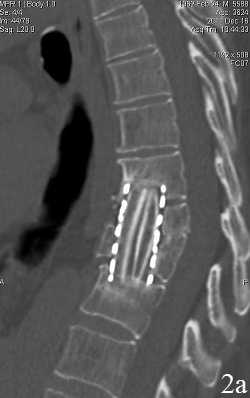

Рис. 1. Пациент В. Титановая блок-решетка без наполнения через 1 месяц (А) и через 12 месяцев (Б) после операции. Нарастание «продавливания» имплантатом кости с увеличением перифокального склероза и резорбции костной ткани

К концу первого месяца после операции (табл. 2) в обеих группах с одинаковой частотой выявлены умеренные реактивные изменения паравертебральных тканей при отсутствии признаков прогрессирования костной деструкции. Вместе с тем, в группе 1 у всех пациентов обнаружено “продавливание” меша в тела блокируемых позвонков на глубину до 1 мм и наличие перифокальной резорбции с отграниченной зоной склероза. В трети случаев у пациентов этой группы угол кифоза увеличился на величину более 5 ° , что не может быть расценено как ошибка измерения. В группе 2 - во всех случаях имплантат плотно соприкасался с телами позвонков без перифокальной резорбции и без нарастания деформации; склеротическая реакция блокируемых тел отмечена у 2 пациентов (8,7%).

При дальнейшем исследовании в сроки 3 мес. и 6 мес. после операции (табл. 3) в обеих группах отсутствовали реактивные изменения в паравертебральных мягких тканях, при этом в группе 1 отмечено нарастание проявлений “вертикальной нестабильности” в виде дальнейшего “продавливания” сеткой тел позвонков на глубину до 3,07±0,8 мм к 3 месяцу и до 3,78±0,7 мм к 6 месяцу с резорбцией и склерозом костного ложа у всех пациентов; больше, чем у трети больных угол деформации в сагиттальной плоскости увеличился более, чем на 5 ° ; лишь в единичных наблюдениях отмечены признаки формирования костного блока в зоне спондилодеза, в то время, как в группе 2 признаки формирования блока между наполнителем меша и реципиентным костным ложем обнаружены уже у большинства пациентов.